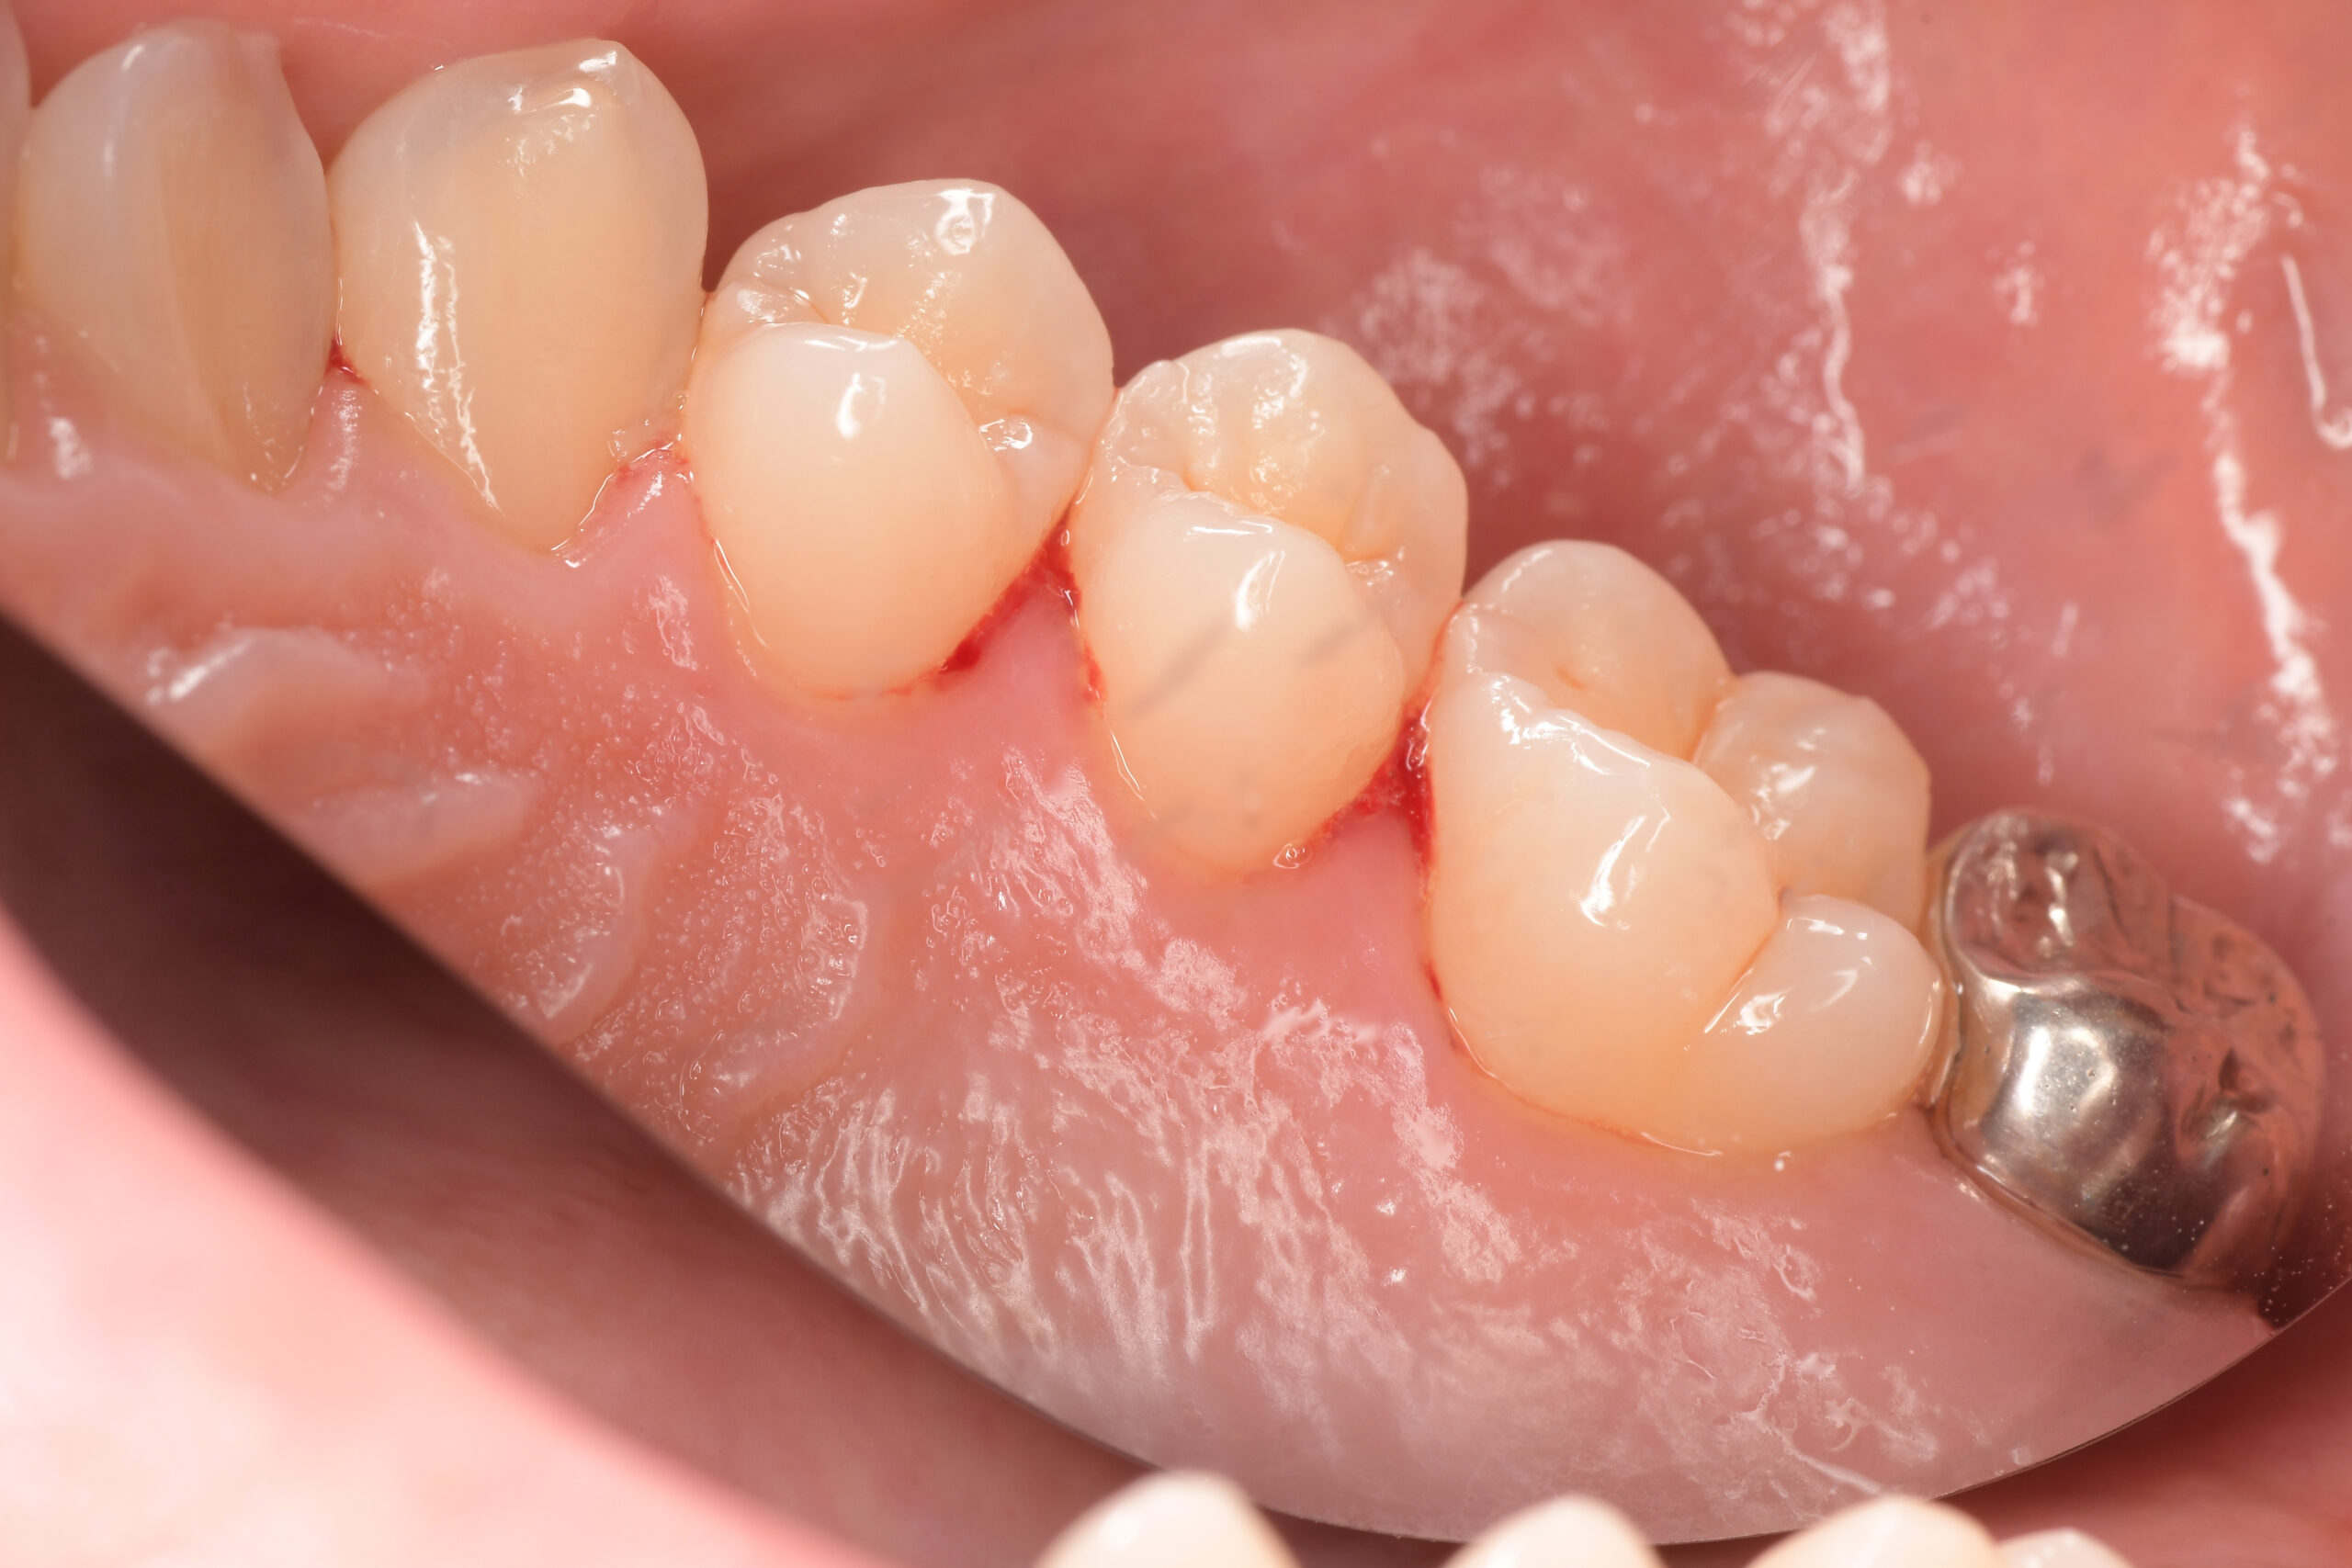

臼歯before

臼歯after

| 年齢・性別 | 27歳・男性 |

|---|---|

| 主訴 | 歯石とりたい |

| 治療内容 | スケーリング |

| 治療期間 | 30分 |

| 治療費 | 約1,500円(保険診療) |

| リスク・副作用 | 知覚過敏、歯肉退縮、出血 |

| 治療方針 | 歯列不正でプラークがつきやすいため、TBIを行い定期的に歯石を除去していきます。 プラークコントロールが出来るようになったら定期検診でクリーニングを行っていきます。 |